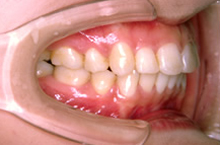

歯並びの幅が広がって、きれいなU字型になってきました。これが本来の歯列の形です。

引っ込んでいた下顎が自然に前に出て、きれいな横顔になりました。

口角がきれいに広がる素敵な笑顔になりました。